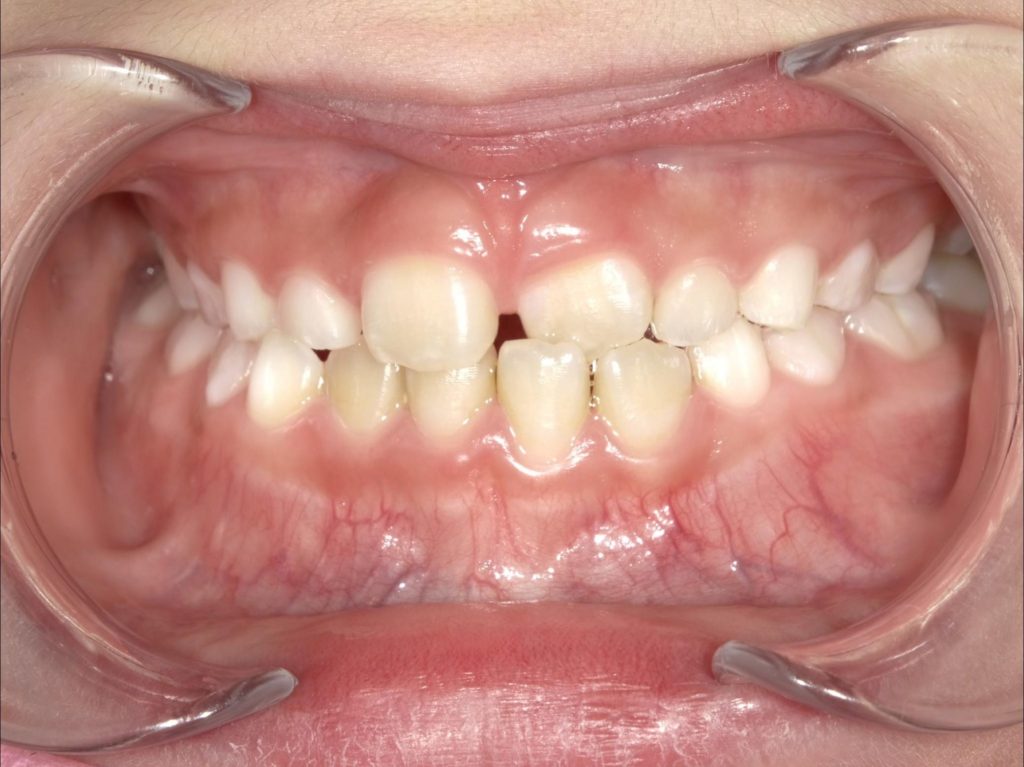

初診時は、

👉 左上の歯が下の歯より内側に入り込み、クロスバイトになっている状態

でした。

👇

📸【Before(治療前)】